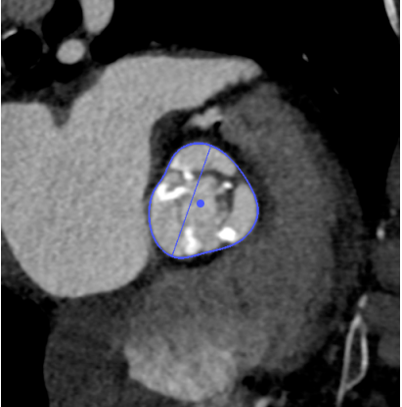

LVOT

长径: 24.3 mm

周长: 66.3 mm

面积: 321.7 mm²

术后1w——冠脉CTA